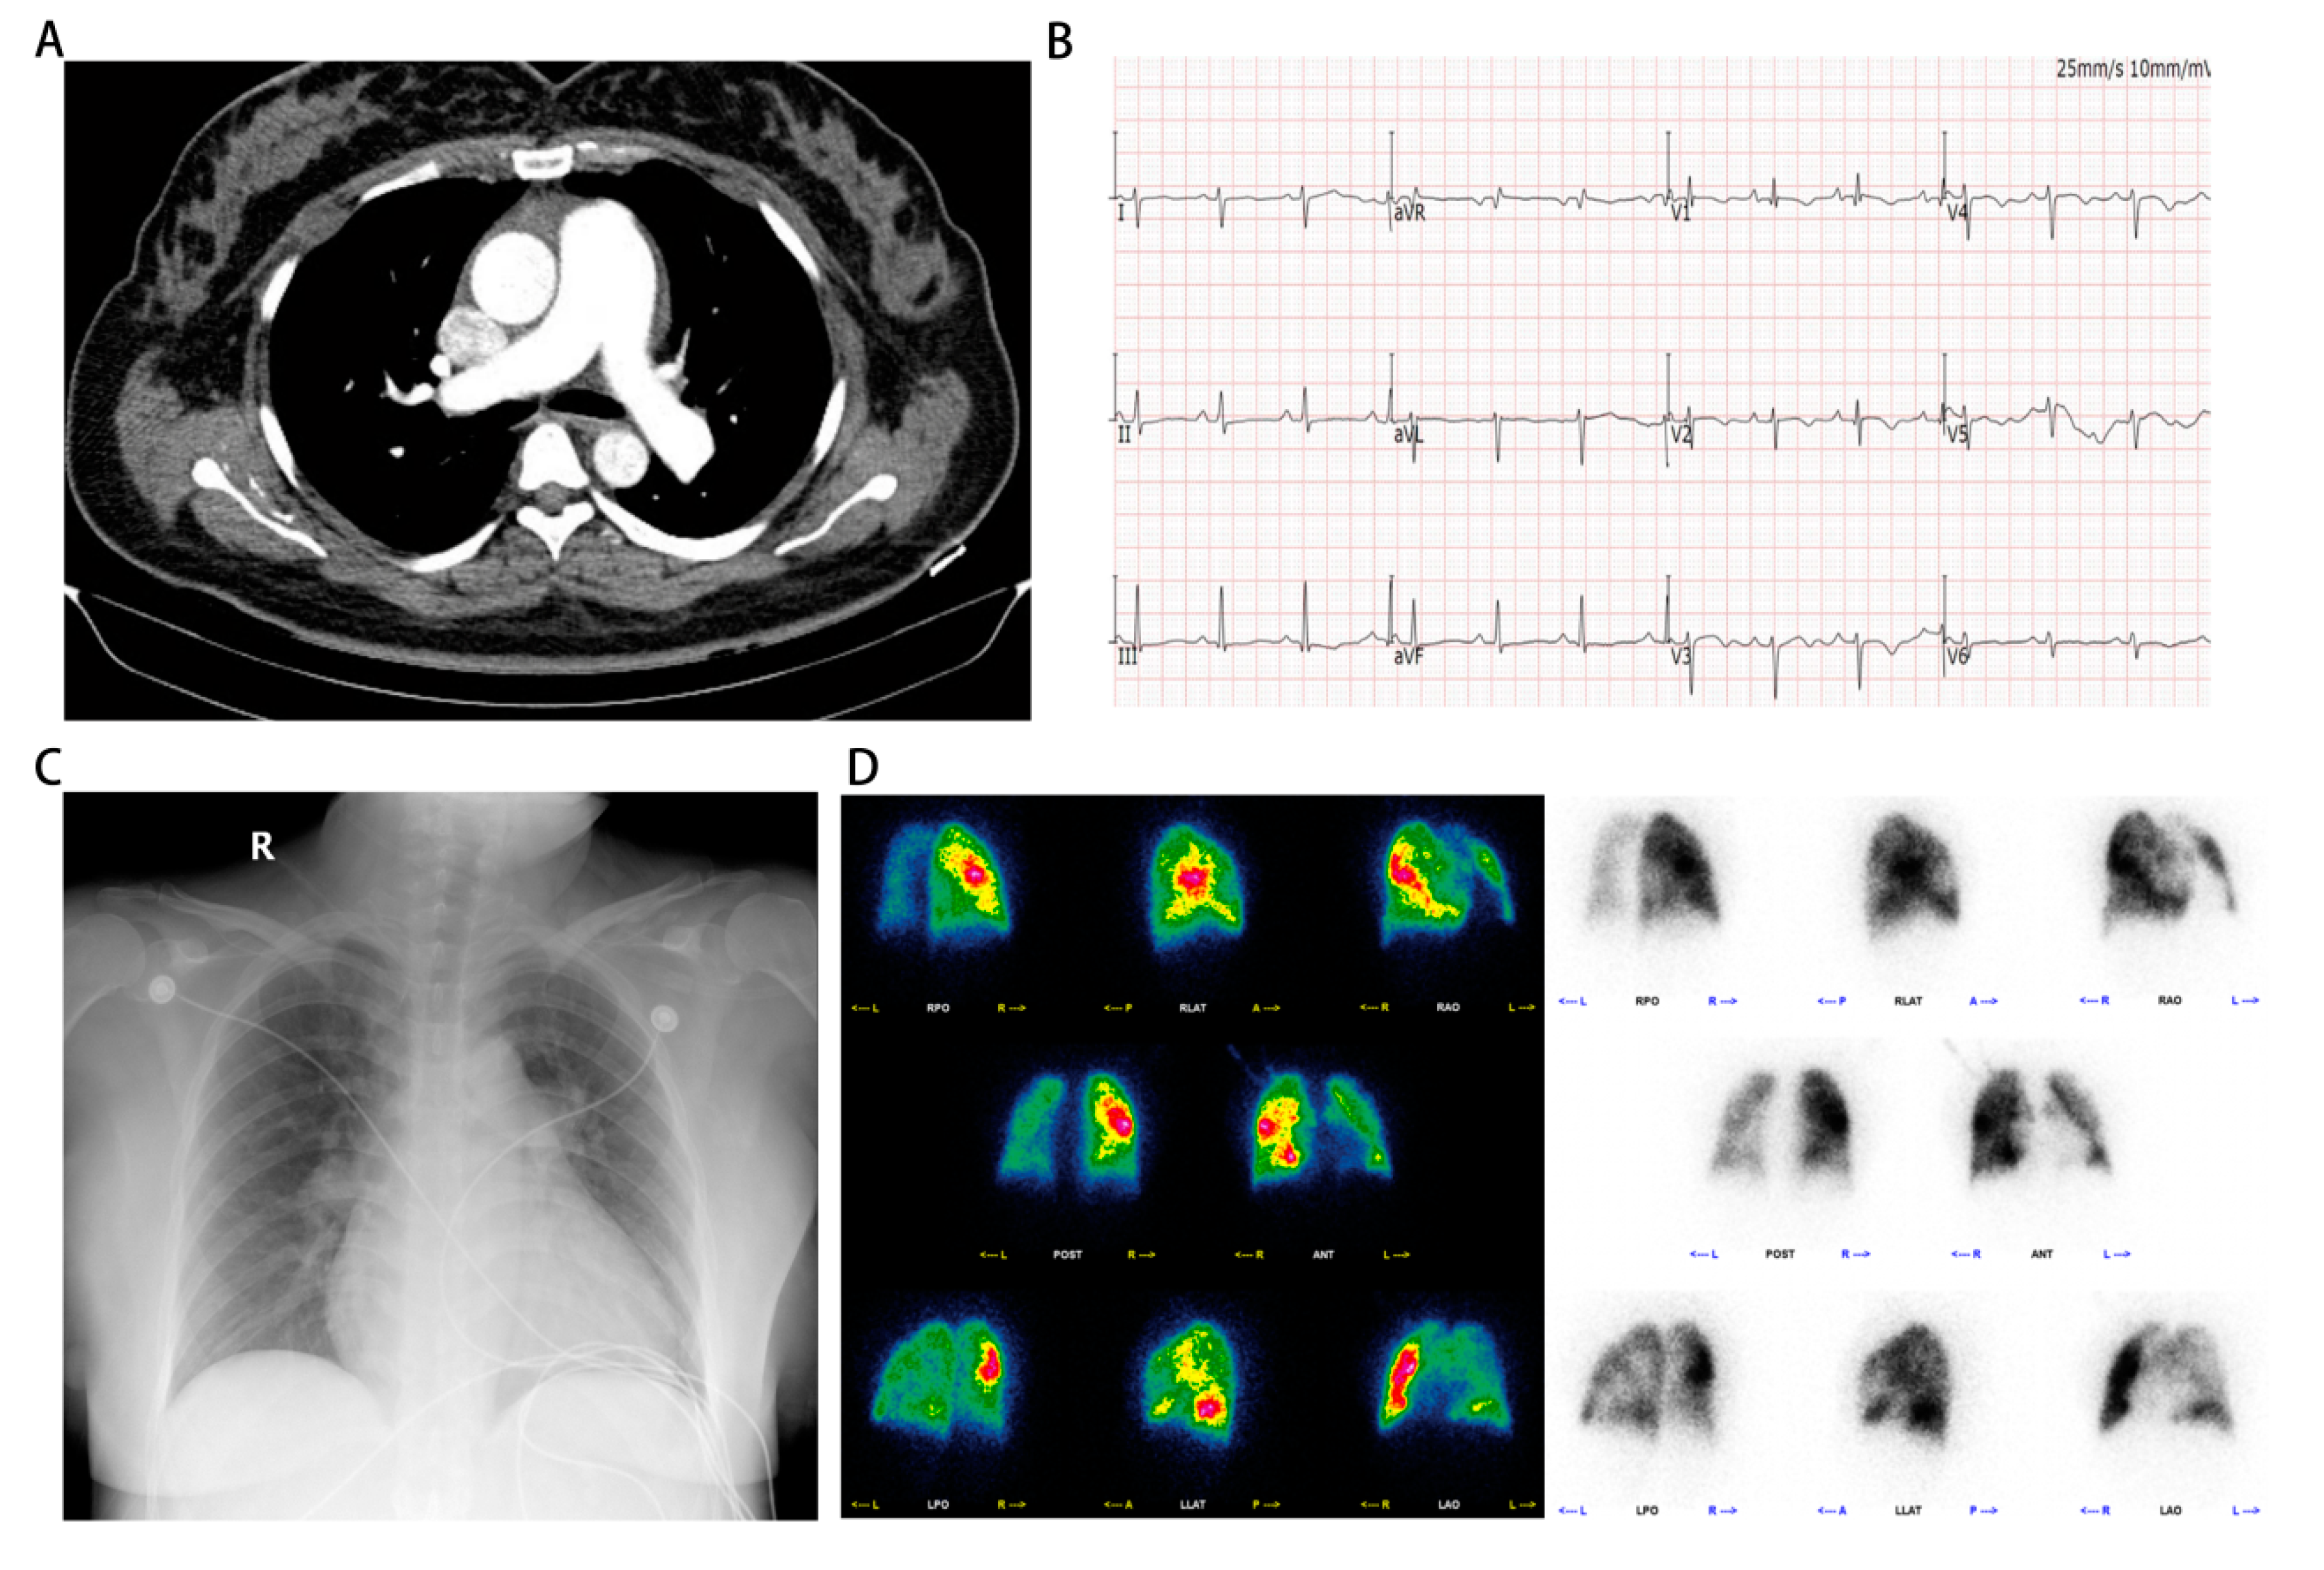

On September 13th, we performed right heart catheterization and pulmonary angiography, yielding the following results: a baseline mean pulmonary artery pressure of 50 mmHg, a mean pulmonary artery pressure of 47 mmHg after inhalation of nitric oxide, a mean pulmonary capillary wedge pressure (PCWP) of 7 mmHg, a pulmonary vascular resistance of 19.99 woods units, and a cardiac output of 2.7 L/min (Figure 2A-C, Table 1 and Supplementary video 6-8). These findings align with the diagnosis of pre-capillary pulmonary hypertension. However, the repeat echocardiography on September 16th revealed a discontinuity of approximately 5mm in the upper part of the interventricular septum and subarterial ventrieular septal defect to be excluded (Figure 3A,B). Thus, we further refined cardiac CTA (Figure 3C,D and Supplementary video 11) then the results showed no obvious atrioventricular shunt or coronary artery stenosis. Combined with the pulmonary artery time delay angiography (Left front tilt 90 degrees, Supplementary video 9), no aorta to pulmonary artery or atrioventricular shunt was observed, we can basically rule out the possibility of pulmonary hypertension caused by congenital heart disease. Finally, it is also possible for this patient to suffer from toxic pulmonary hypertension as a result of her drug use. Nevertheless, given the long interval between drug use and patient onset, as well as the time this patient with no special discomfort, we eliminated toxin-induced pulmonary arterial hypertension.

Figure 3. The images of echocardiography and cardiac computed tomography angiography. (A, B) Echocardiography on September 16th showed a discontinuity of approximately 5 mm in the upper part of the interventricular septum and subarterial ventrieular septal defect to be excluded. (C, D) Cardiac computed tomography angiography showed no obvious atrioventricular shunt or coronary artery stenosis.